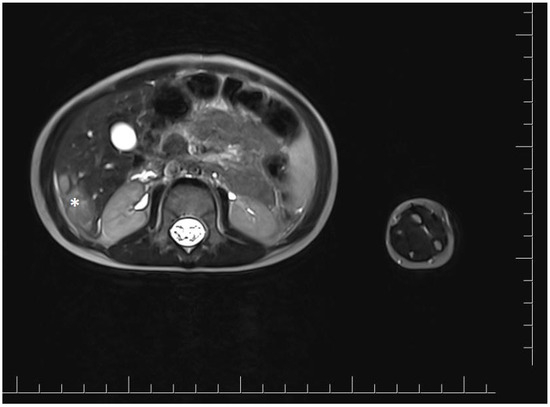

2. Case Report